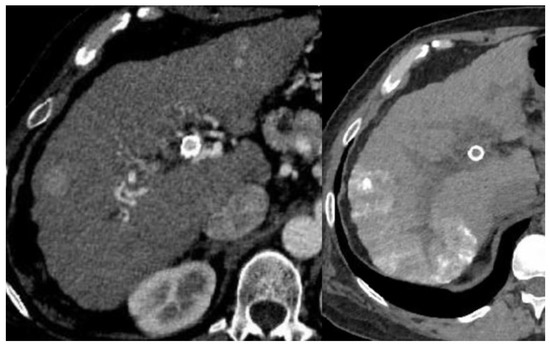

- Brancatelli, G.; Federle, M.P.; Grazioli, L.; Carr, B. Hepatocellular Carcinoma in Noncirrhotic Liver: CT, Clinical, and Pathologic Findings in 39 U.S. Residents. Radiology 2002, 222, 89–94. [Google Scholar] [CrossRef] [PubMed]